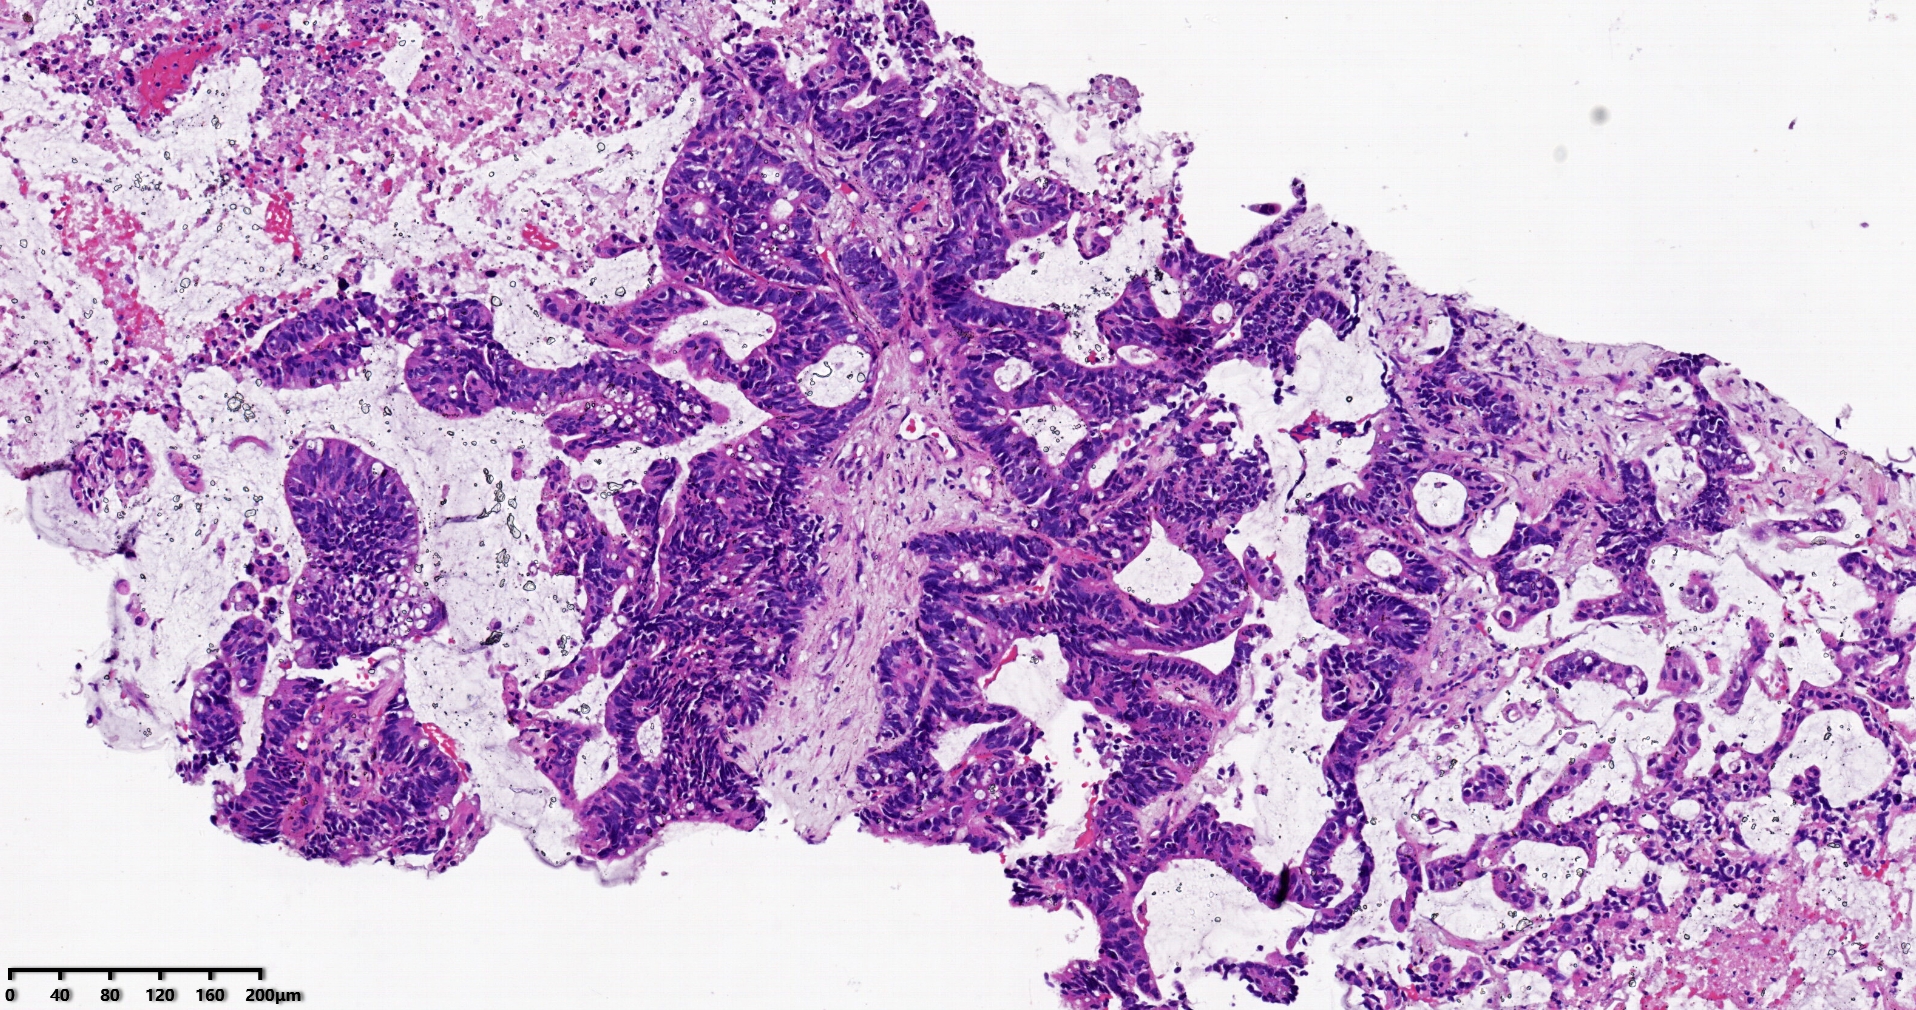

标本名称肝脏穿刺

大体所见灰白灰红色穿刺活检组织两条,长1.7-1.9cm,直径0.1-0.2cm。

考虑符合:肝内胆管癌

考虑转移性黏液腺癌,消化道来源可能,建议做免疫组化,排除胆管源性。